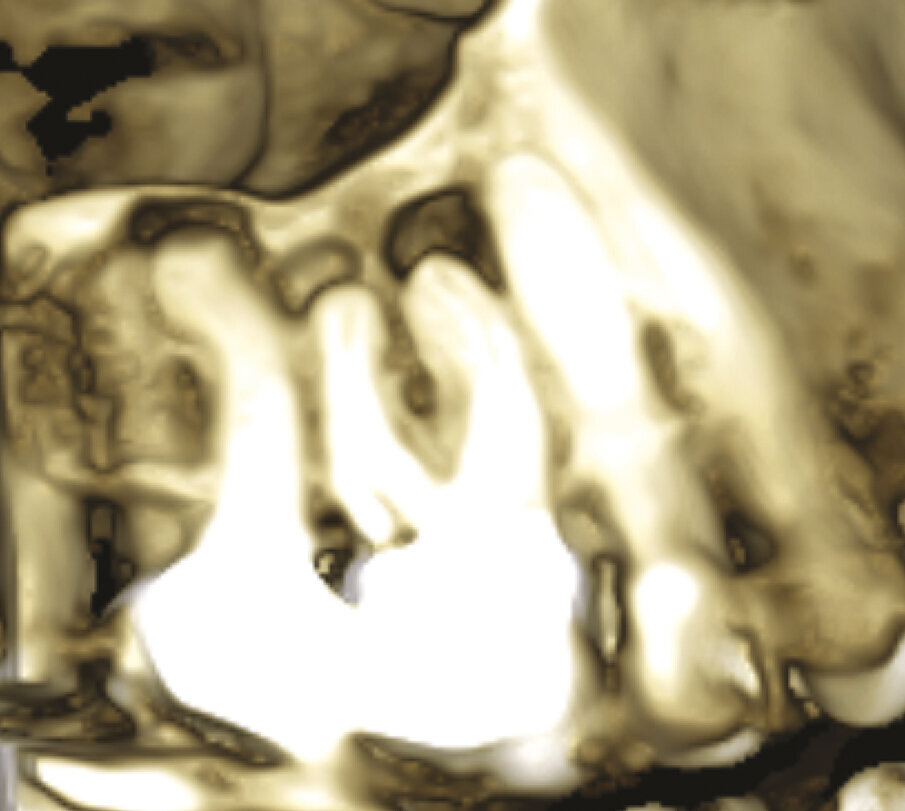

Fig. 1a - Il paziente è stato inviato per la terapia chirurgica della radice mesiovestibolare del primo molare superiore di destra.

Fig. 1c - La CBCT mostra il riassorbimento dell’osso corticale adiacente la radice distovestibolare.

Figg. 1d, 1e - Un’altra lesione periapicale sta interessando il secondo molare.

Fig. 1f, 1g - La sezione sagittale mostra ancora meglio le lesioni a carico del primo molare su entrambe le radici vestibolari e le lesioni a carico di entrambe le radici vestibolari del secondo molare, il cui canale MB1 appare completamente vuoto.